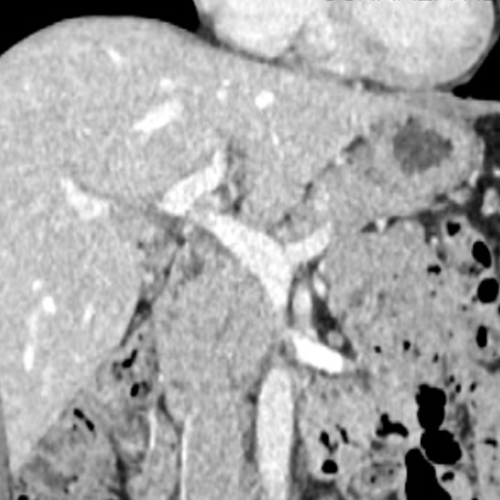

Le foie est divisé en 8 segments indépendants (classification de Couinaud), possède une double vascularisation (veine porte et artère hépatique) et les voies biliaires .

Le TDM hépatique dure environ 10 minutes. Le manipulateur vous guidera . Il sera nécessaire de rester strictement immobile. Une injection de produit de contraste à base d’iode est souvent réalisée. On réalise souvent un protocole « triphasique » (passage sans contraste, puis phase artérielle et phase portale). Une phase tardive est souvent réalisée.

- Les tumeurs malignes : Carcinome Hépatocellulaire (CHC), Métastases, Cholangiocarcinome